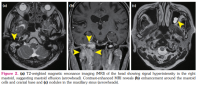

An 80-year-old man with a history of diffuse large B-cell lymphoma (DLBCL) presented to the otolaryngology department due to hearing loss and fullness in the right ear. He was diagnosed with primary testicular DLBCL five years earlier, but complete remission was sustained after treatment. Computed tomography identified a soft-tissue mass in the right middle ear and mastoid cells, along with destruction of the petrous and sphenoid bones with soft-tissue mass and mucosal thickening in the maxillary sinus (Figure 1a-c). A weakly positive result was obtained for serum proteinase 3-anti-neutrophil cytoplasmic antibody (PR3-ANCA), at 5.2 IU/mL. The patient was referred to our department on suspicion of granulomatosis with polyangiitis (GPA) and otitis media with ANCA-associated vasculitis (OMAAV). He showed no other symptoms suggestive of systemic vasculitis, and serum soluble interleukin-2 receptor was slightly elevated to 643 U/mL (normal: <610 U/mL). The T2-weighted magnetic resonance imaging (MRI) showed signal hyperintensity in the right mastoid, suggesting mastoid effusion (Figure 2a). However, contrast-enhanced MRI revealed enhancement around the mastoid cells and cranial base and nodules in the maxillary sinus (Figure 2b, c). Diffuse large B-cell lymphoma was diagnosed from biopsied mucosa in the maxillary sinus, with no findings of granuloma or vasculitis.

Positive results for ANCA are sometimes seen in patients with infection, inflammatory bowel disease or malignancy, including malignant lymphoma (ML), and not just in cases of vasculitis.[1,2] The precise mechanisms remain unclear, but neutrophil infiltration in response to tissue damage by ML or lymphoid cell-derived factors have been hypothesized to produce ANCA.[3] Some reports have described cases of ML mimicking GPA with craniocervical or otolaryngologic manifestations, such as sinusitis, otitis, nasal obstruction and discharge, masses in the nasal cavity, hypertrophic pachymeningitis and infarction of the pons.[4,5] Although GPA was suspected due to craniocervical or otolaryngologic manifestations in these patients, no kidney involvement was found.[4] Malignant lymphoma should, thus, be considered in patients without typical presentations such as glomerulonephritis, but differentiating between the two entities is practically difficult. A previous study comparing ANCA-positive patients with a clinical diagnosis of AAV from those without a clinical diagnosis of AAV demonstrated that a higher ANCA titer (≥4 times the upper limit of normal) and the number of affected organ systems (≥2 organ systems) may help to discriminate AAV from other diseases with positive results for ANCA.[2] A study investigating the characteristics of primary skull base lymphoma showed the usefulness of MRI to distinguish ML from other pathologies mimicking ML.[6] The combination of imaging findings, restricted diffusion on diffusion-weighted imaging, surrounding hyperostosis, bony erosion and/or marrow signal replacement, and heterogeneous contrast enhancement may raise suspicion for skull base lymphoma.[6] Our patient exhibited a lower ANCA titer, and a soft-tissue mass in the right middle ear and mastoid cells, along with destruction of the petrous and sphenoid bones and contrast enhancement of the mass on MRI without other organ involvements, suggesting ML. As a result, ML should be excluded using the degree of elevation of the ANCA titer, affected organ systems and MRI findings, when GPA limited to the ears, nose and throat is suspected.